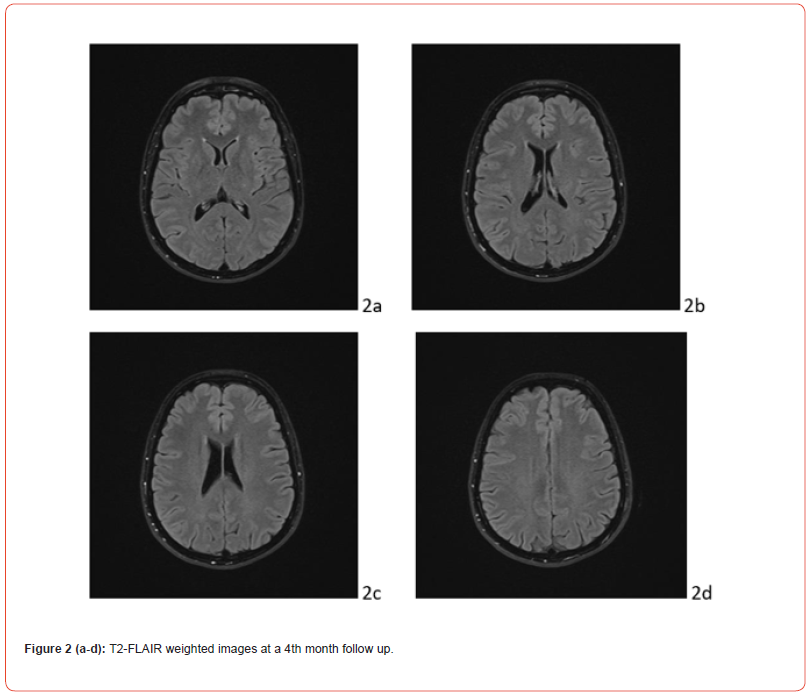

In the post-critical phase, the patient appeared in a mild state of confusion with amnesia of the event. Vital signs continuously monitored from the first episode were normal, except for a BP measurement of 155/90 mmHg. The patient underwent neuroimaging. Cranial computerized tomography showed a swelling of the genienal soft tissues on the left, with tenuously hyperdense tissue, related to mild extravasation of blood, because of the trauma. T2 FLAIR MRI showed alterations in the cortico-subcortical signal, not only in bilateral parieto-occipital regions, but also in frontal lobes and at the vertex (Fig.1 A). Clinical picture, supported by MRI findings, confirmed the diagnosis of PRES. Anti-inflammatory, analgesic, anti- epileptic, anti-hypertensive and anti-oedema therapy was set up according to the following scheme: Perfalgan 1000 mg 1 vial, bid, iv; Decadron 4 mg 1 vial x 3, iv; Levetiracetam 500 mg/5 ml 2 vials in 500 ml 0,9% sodium chloride solution in 24 hours, Nimodipine 5 drops x 3, after BP control; osmotic therapy was suggested in case of symptoms and signs of intracranial hypertension. During post-critical observation, vital signs were normal, except for a BP value of 152/94 mmHg. The hydroelectrolyte balance and blood chemistry tests were normal. The condition of the patient improved rapidly. At day 9, the patient was discharged wit maintenance therapy and an indication of follow-up at one month. The last EEG and MRI check, performed at month IV, showed a complete regression of the clinical picture (Figure. 1 B).

MRI of the brain is the gold standard diagnostic tool. It allows early detection of diffuse vasogenic oedema of the white matter, its posterior site, in the parieto-occipital regions, extent of damage, differential diagnosis with other pathological conditions. The peculiar lesions of PRES are symmetrical, hypointense in T1-weighted sequences, hyperintense in T2-weighted and T2 FLAIR sequences, isointense or mildly hyperintense in DWI. They have a watershed pattern [29]. Apparent diffusion coefficient (ADC) maps may show normal or increased diffusion in the case of vasogenic edema (signal hyperintensity), restricted in the case of cytotoxic edema (signal hypointensity). Following gadolinium administration, linear or perimetral enhancement (gyrus-like) was observed in 20% of patients. PRES is considered mild when cortical and subcortical white matter oedema is present, without mass effect, herniations, hemorrhages, minimal involvement of another region (cerebellum, brainstem, basal nuclei). Moderate PRES is defined by the presence of confluent oedema extending from the cortex to the deep white matter without extension to the periventricular regions or mild involvement of two of the other regions indicated above (cerebellum, brainstem and basal nuclei). A mild mass effect may be present, without herniations or midline shifts, hemorrhages. Severe PRES is characterized by confluent oedema extending from the cortex to the ventricles, midline shift or herniation due to oedema or hemorrhage, involvement of three other regions (cerebellum, brainstem, and basal ganglia) [30]. As mentioned above, DWI sequences and ADC maps are useful for distinguishing vasogenic edema from cytotoxic edema, typical of hypoperfusion in cases of cerebral infarction or other conditions, such as inflammatory, demyelinating and space-occupying lesions. However, small areas of restriction of diffusion and large areas of vasogenic oedema are found in 15-33% of PRES patients [31,32]. These, hyperintense in DWI, hypointense in ADC maps, indicate cytotoxic edema and are predictive of incomplete recovery and poor prognosis [33]. The study of intracranial vessels with MRI with angio sequences, CT angiography and transcranial Doppler ultrasound are indicated for the differential diagnosis with reversible cerebral vasoconstriction syndrome, which also appears with intense headache in the postpartum period [34]. Cerebral hemorrhages are found in 10–30% of cases.

Arterial Spin Labeling MRI showed hyperperfusion in the majority of PRES patients. However, conflicting results are reported on perfusion images. Considering time of imaging, hyperperfusion is detected in acute phase, hypoperfusion in subacute phase [37]. The evolution of PRES is usually benign and is closely linked to the timeliness of diagnosis and therapy. However, residual vascular parenchymal brain damage may be observed [31].